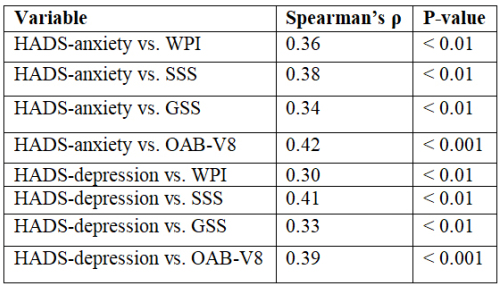

Duygu Kurtuluş, Selma Dağcı, Ferhat Yakup Suçeken, et al.

Fibromyalgia (FM) is a chronic, centralized pain disorder

characterized by widespread musculoskeletal pain, fatigue,

cognitive dysfunction, and a variety of somatic symptoms.

Beyond its hallmark pain features, FM frequently presents

with genitourinary complaints, including lower urinary tract

symptoms (LUTS) such as urinary urgency, frequency, and

nocturia. Among these, overactive bladder (OAB) has gained

attention as a functionally significant and underrecognized

component of the FM symptom complex [,].

The pathophysiology of FM and OAB is believed to share

common mechanisms, most notably central sensitization-a state

of amplified neural signaling in the central nervous system

that leads to heightened pain and sensory perception [,]. In

both disorders, dysregulation of the autonomic nervous system,

altered pain processing, and neurogenic inflammation have been

implicated. These shared neurobiological pathways suggest

that OAB in FM may not merely be coincidental but rather a

manifestation of overlapping central dysfunction [,,].

In parallel, psychiatric comorbidities-particularly anxiety

and depression-are prevalent in both FM and OAB populations.

Up to 60–70% of FM patients experience clinically significant

symptoms of depression or anxiety, which have been shown

to exacerbate pain, fatigue, and somatic burden []. Similarly,

psychological distress has been associated with increased

urinary urgency and incontinence episodes in patients with OAB,

potentially through heightened arousal, cortical hypervigilance,

and altered bladder perception [,].

Although the independent associations of psychiatric

symptoms with FM and OAB are well documented [,]

limited data exist regarding their combined burden in patients

experiencing both conditions [,]. In particular, the

impact of psychiatric comorbidity on symptom severity and

functional status in FM patients with OAB remains poorly

understood [,]. Elucidating this relationship may inform the

development of more integrative treatment strategies [,].

The present study aimed to investigate the prevalence and

clinical significance of anxiety and depression in FM patients

diagnosed with OAB, using validated screening instruments.

We further evaluated the relationship between psychiatric

symptom burden and FM/OAB severity to better understand the

interplay between psychological distress and visceral-somatic

sensitization in this patient population.